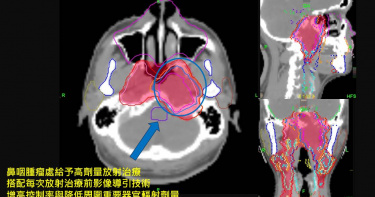

48歲男不菸不酒竟罹鼻咽癌 「影像導引合併螺旋刀」重獲健康

台灣為鼻咽癌高發生率之國家,其初期症狀不易察覺,常被誤以為是慢性或過敏性鼻炎。48歲的蔡先生,5年前因脖子莫名腫大、長期鼻塞且出現複視症狀,前往亞東醫院就診,平常沒有抽菸喝酒嚼檳榔習慣的他,被確診為鼻咽癌第四期。在亞東醫院頭頸癌多專科照護團隊的治療下,蔡先生的腫瘤已經完全消失,不僅讓他擺脫了健保卡上的重病註記,更讓他重回一般民眾的生活。亞東醫院耳鼻喉部廖立人主任與放射腫瘤科謝忱希主任召集頭頸癌多專科照護團隊,共同評估最佳的治療方案,並決定採用「前導化學治療合併同步性放化療方式」為治療策略,同時運用「影像引導合併螺旋刀技術」治療。針對鼻咽腫瘤區域,實施高劑量放射治療,並搭配每日放射治療前的影像引導調教技術,確認腫瘤位置,即時修正誤差,提高原發處腫瘤與轉移淋巴結消融控制率,降低周圍重要器官的傷害。接受頭頸癌多專科照護團隊七周治療後,患者的腫大淋巴結及眼中雙影的情況完全消失。在過去5年,除了接受團隊照護,更積極參與復健課程,蔡先生的鼻咽內視鏡、磁振造影及人類疱疹病毒第四型病毒量等檢查均未顯示轉移或復發情形,腫瘤已經完全消失,鼻咽功能也恢復正常,蔡先生終於能夠取消健保卡上的重病註記,重返一般民眾身分,他激動地表示:「謝謝醫院頭頸癌團隊的用心與鼓勵,讓我戰勝癌症,我終於成功了!」台灣與中國東南沿海各省是鼻咽癌的高危險發生區。根據衛生福利部109年癌症登記報告顯示,鼻咽癌發生率排名中,男性為第14位、女性為第20位,儘管各年齡層皆有罹癌可能,但仍以40-60歲年齡層的患者居多。謝忱希主任指出,目前導致鼻咽癌的原因尚未完全釐清,種族、地區、性別和遺傳因子都可能是潛在因素;此外,環境因子如攝取鹽漬或煙燻的食物、進香拜拜或抽菸等,也有報告指出可能與鼻咽癌相關。在鼻咽癌患者的血清中,人類疱疹病毒第四型病毒指數通常較高,然而,該病毒與鼻咽癌的確切關係截至目前仍未完全明瞭。廖立人主任表示,鼻咽癌在早期的治愈率可達90%,但因初期無明顯症狀,患者容易忽略,確診時,多已進入中後期,其症狀可能有眼皮下垂、臉麻嘴歪、吞嚥困難或聲音沙啞等。廖主任提醒,若民眾出現鼻塞、鼻涕帶血絲、耳鳴或耳塞、不明原因的脖子腫塊不退、臉部麻痺、複視或頭痛等症狀,應盡快至耳鼻喉科就診,切勿延誤。在治療方面,謝忱希主任也說明,鼻咽癌的治療方式包括放射線治療、化學治療、免疫治療等。針對初期鼻咽癌,常以治癒性放射治療為主,中晚期則主要採用同步性放化療或引導性化學治療合併同步放化療等方法,如同蔡先生,只要患者積極配合治療團隊,仍然能夠獲得良好的治療結果。亞東醫院林子玉副院長表示,現代生活的快節奏和壓力是難以避免的現象,我們更應該謹慎關注自己的生活習慣,維持良好的生活環境。在飲食方面,民眾應當注重均衡飲食,避免攝取過量的高鹽、高油、高糖食物,並增加蔬果和高纖維食物的攝取。同時減少抽菸和限制飲酒,並定期接受健康檢查以保障身體狀況。